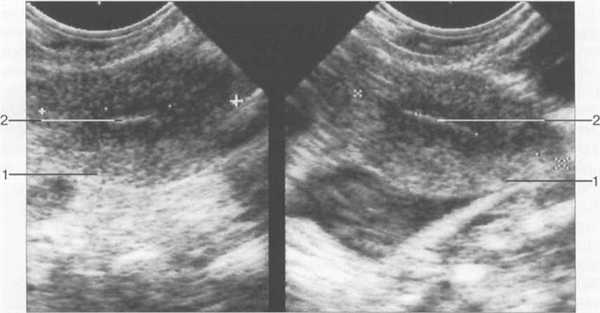

Величина М-эхо к 14-му дню МЦ (периовуляторный период) у женщин детородного периода может составлять до 14 мм. На протяжении 1 недели после овуляции эхогенность эндометрия продолжает нарастать — сначала в базальной зоне, а затем в поверхностных отделах; появляется ободок пониженной эхогенности. К 21-му дню МЦ эндометрий становится полностью гиперэхогенным (за счет накопления в клетках секрета), по периферии выявляется гипоэхоген-ная зона (обусловленная расширенными сосудами миометрия на границе с базальным отделом эндометрия) (рис. 15.3, б; 15.4, б ). Высота эндометрия остается прежней (как в 1-й фазе), но к моменту наступления менструации отмечается некоторое уменьшение его высоты.

В постменопаузальном периоде М-эхо представляет собой структуру высокой эхогенности шириной 1—2 мм, гипоэхогенный ободок вокруг эндометрия отсутствует (рис. 15.5). Иногда полость матки расширена до 2—4 мм из-за наличия в ней небольшого количества жидкости, что обусловлено снижением тонуса миометрия. Для исключения предраковых процессов в эндометрии (дисплазии) требуется проведение диагностических мероприятий и наблюдение в динамике.

Рис. 15.5. М-эхо в постменопаузе, трансвагинальное сканирование.